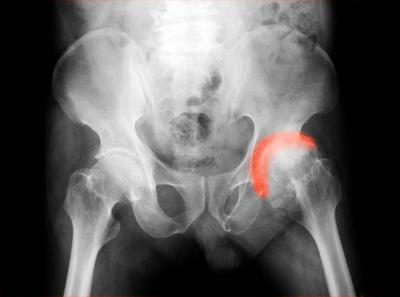

髌骨半脱位怎样治疗【双膝髌骨半脱位】

如果是前一种情况在关节镜下松解髌骨外侧支持带即可,手术创伤小恢复快。如果是后一种情况就需要做胫骨结节移位。具体治疗方案得靠查体仔细评估。像现在的脱位角度只进行股四头肌的练习基本作用不大。

习惯性髌骨脱位一般采用手术治疗。手术当天:麻醉消退后,开始活动足趾;如疼痛不明显,可尝试股四头肌等长练习。术后第1天:(1)踝泵:5分钟/组,1组/小时。

采用综合手术治疗。并倡用股内侧肌移位加强内侧牵拉力量。手术方法是:将膝关节外侧挛缩的软组织松解。将膝内侧关节紧缩缝合并将股内侧肌止点移到髌骨外侧。根据具体情况做Houser手术或Goldthwait手术。

力量训练也是需要的,你看看几种经典的下肢力量练习方式一文中“抗阻伸膝”动作,注意强调完全伸直并在充分伸直位到微屈30度之间完成动作,强化“股内侧肌”,用肌肉的张力进一步束缚髌骨阻其脱位。

髌骨习惯性脱位的原因很多。不管什么原因,都需要手术治疗,消除脱位的原因(比如骨畸形、膝外翻、内侧支持带松弛、外侧支持带挛缩等)。